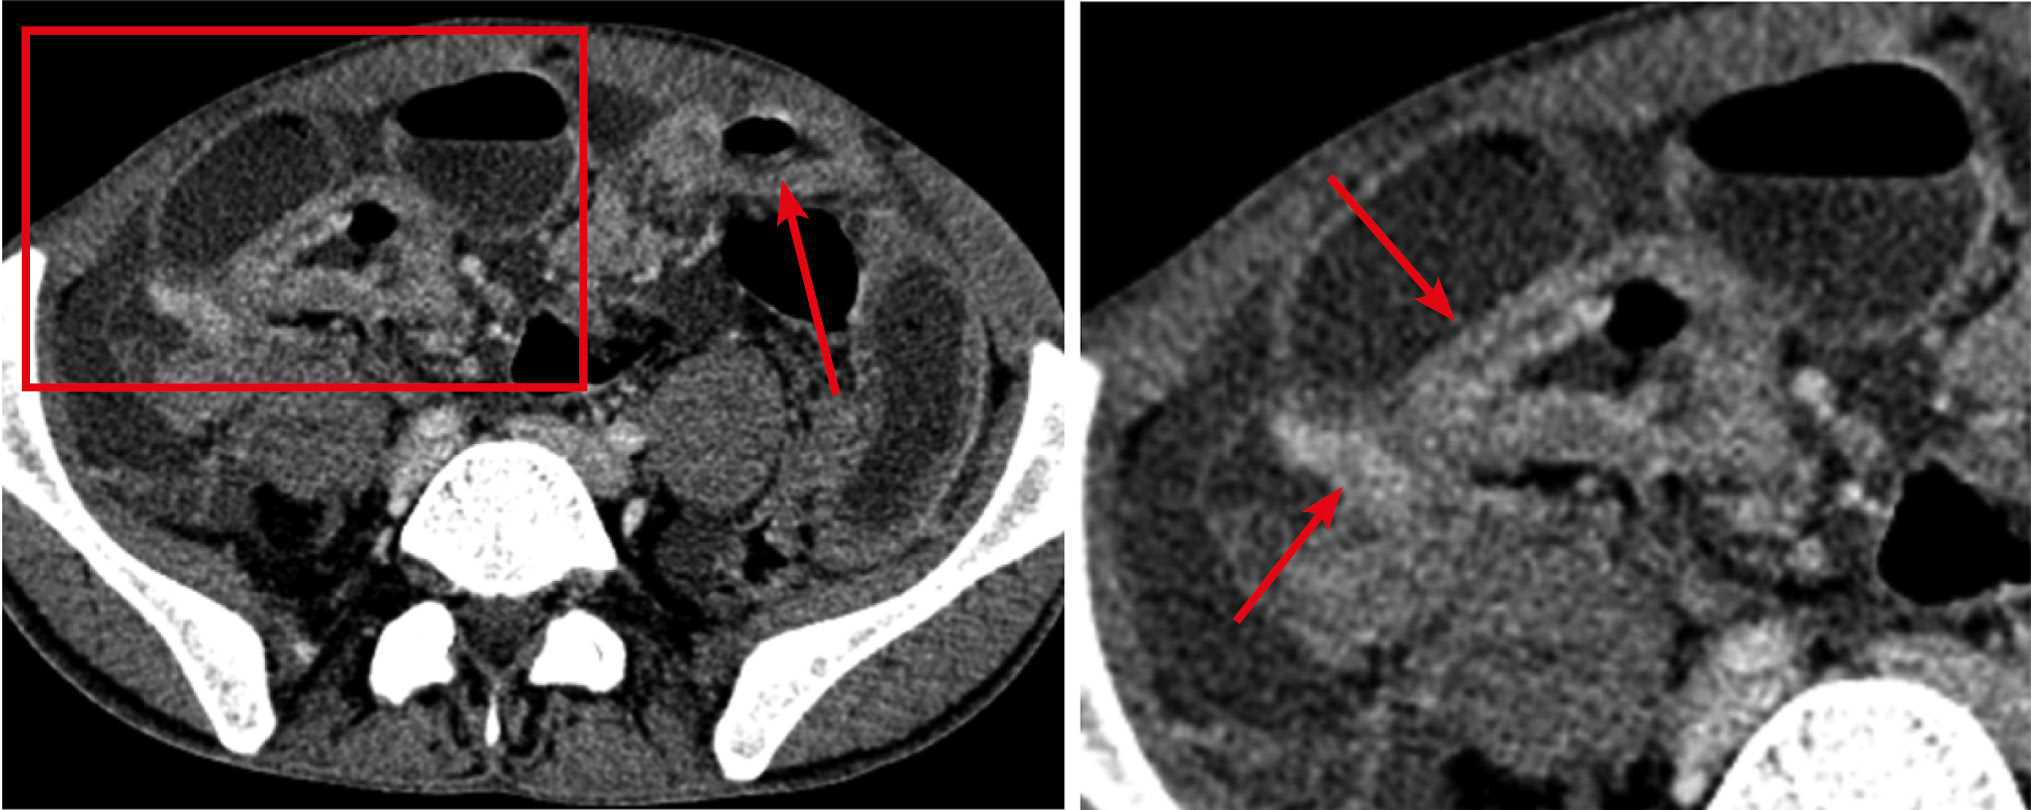

Рис. 8. Больная, 58 лет. МСКТ: рак тощей кишки. Венозная фаза контрастного усиления (накануне выполнялось контрастирование просвета кишки per os, поэтому в просвете толстой кишки наблюдается остаточное контрастное вещество

Примечание. А — аксиальная томограмма, Б — сагиттальная реконструкция. Стенка тощей кишки на протяжении ~150 мм утолщена до 10 мм. Просвет кишки неравномерно сужен. Контрастное усиление стенки трансмуральное, изоденсивное с остальными отделами кишки (стрелки). Имеется уплотнение прилежащей части брыжейки за счет десмопластической реакции (пунктирная стрелка).

Для экзофитной формы рака характерен преимущественно узловой рост в просвет кишки. Визуально злокачественные опухоли такого типа напоминают гриб на широком основании. Иногда встречаются экзофитные опухоли блюдцеобразной и полипозной формы, широко прилежащие к стенке кишки и обтурирующие ее просвет [24]. При всех анатомических формах роста опухоли кишки в патологический процесс вовлекаются регионарные лимфатические узлы брыжейки: они уплотняются, их объем увеличивается, максимальный размер по ширине обычно достигает 10 мм и больше. В наших наблюдениях при контрастном усилении ткань опухоли контрастировалась трансмурально, неравномерно, интенсивность контрастного усиления не отличалась от таковой неизмененной стенки кишки (рис. 9). Экзофитные формы поражения сопровождались различной степени выраженности престенотическими расширениями просветов.

Рис. 9. Больная, 53 года. МСКТ: рак дистального отдела подвздошной кишки. Тонкокишечная непроходимость

Примечание. А — аксиальная томограмма, Б — сагиттальная реконструкция томограммы. Артериальная фаза контрастного усиления. В дистальном отделе подвздошной кишки на протяжении 10 см определяется экзофитное образование, суживающее просвет (стрелки). Опухоль трансмурально накапливает контрастный препарат. В тонком кишечнике имеются признаки компенсированной тонкокишечной непроходимости.